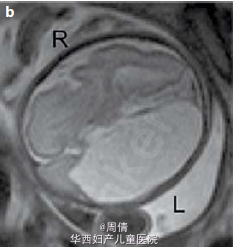

1,2.超声提示在大动脉分叉点以上的降主动脉上有一个动脉瘤,最大直径2cm 3,可见扩大的左脑室和变薄的左侧大脑实质 4,30周时胎儿MRI提示颅腔内的左侧脑室有一个增大的囊性结构

诊断为先天性腹主动脉瘤合并脑穿孔 继续妊娠,孕40周时孕妇产下一个2770g的男婴 体检提示婴儿腹部有一直径2cm的肿块 腹部CT提示降主动脉处有一直径2cm的动脉瘤 脑部CT提示左侧脑室有一囊性结构 出生第三天,MR血管造影提示胎儿期的左颈内动脉阻塞 婴儿6个月时复查腹部CT,提示降主动脉动脉瘤无明显增大,左肾动脉狭窄 因为移植如此小的血管困难太大,所以并未进行手术治疗 但是使用了VP分流器来阻止脑积水的进展